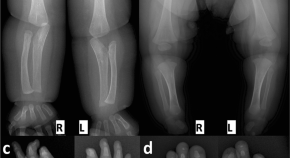

Andrea Superti-Furga, Ron Wevers, Clara van Karnebeek, Luisa Bonafé and colleagues identify mutations in NANS, which encodes the sialic acid synthase, in nine individuals with severe infantile-onset developmental delay and skeletal dysplasia. They describe abnormal metabolites accumulating because of deficient NANS enzyme activity and show that impaired sialic acid synthesis in zebrafish perturbs skeletal development, which can partially be rescued by supplementation with exogenous sialic acid.